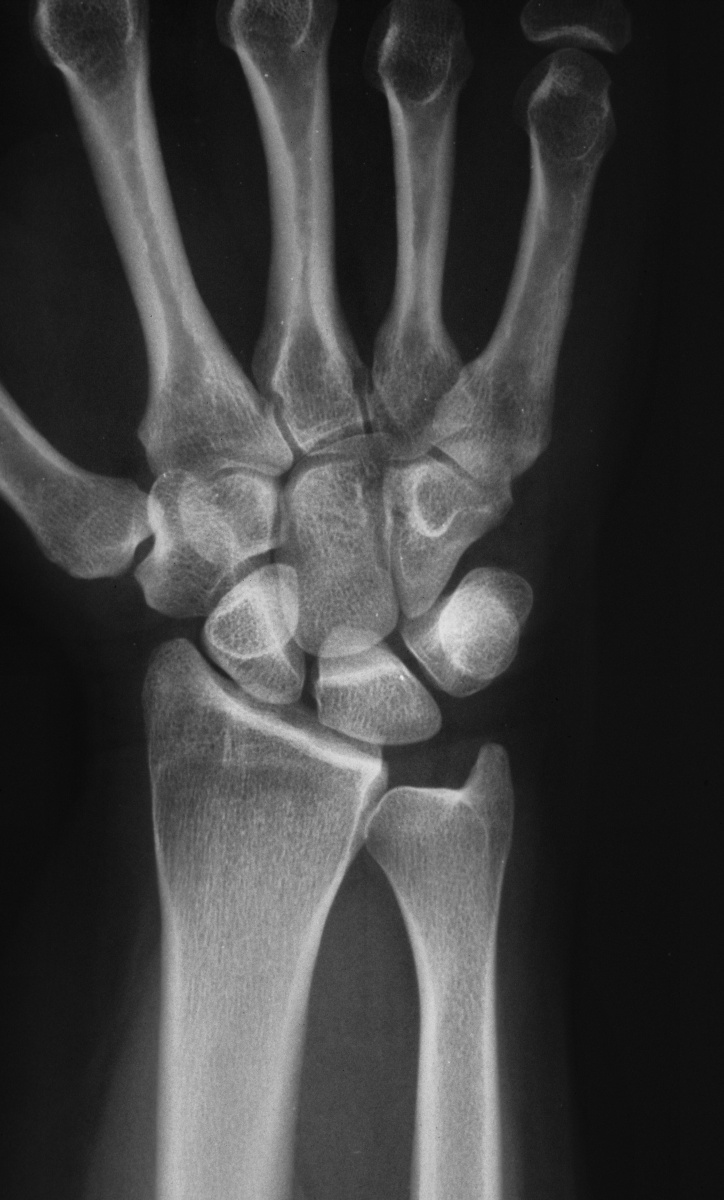

| This woman in her 30's presented with left wrist pain and was found to have inflammatory osteoarthritic changes throughout her wrist, distal radioulnar joint and thumb basal joint. Blood tests were normal, including rheumatoid factor, antinuclear antibody, sedimentation rate, uric acid, and complete blood count. She was treated with nonsteroidal oral antiinflammatory medication and splints. |

| Initial Films: |